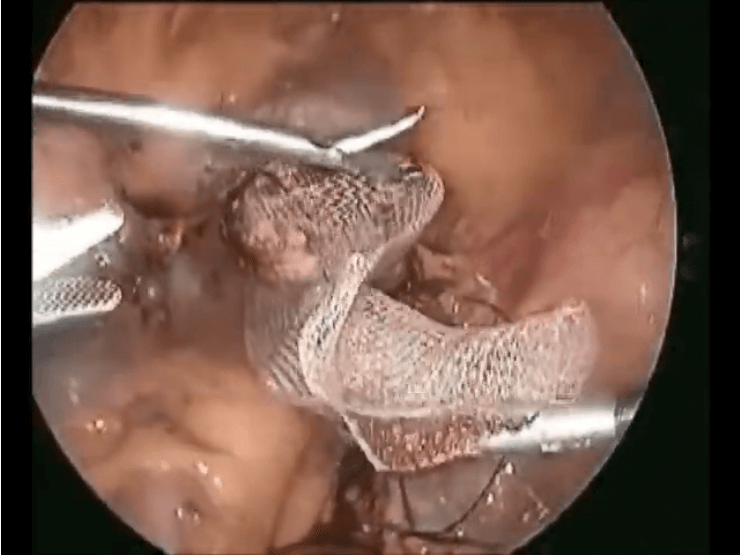

Laparoscopic Sacrocalpopexy for vaginal Vault prolapse - Live Demonstration